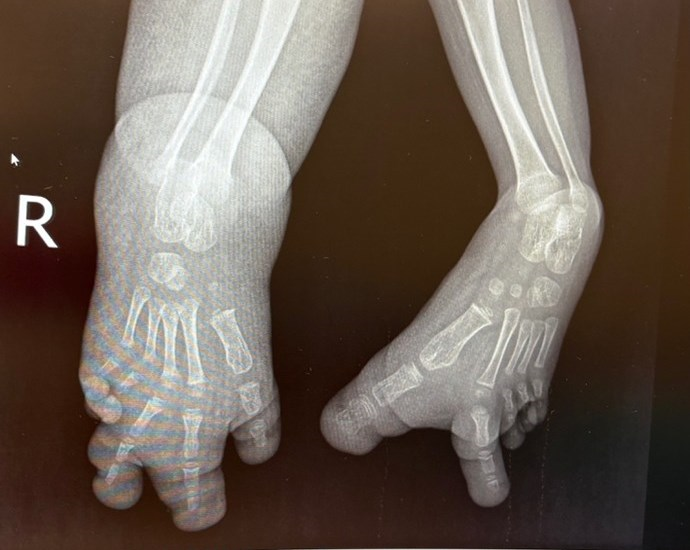

• Macrodactyly bilateral feet – right central ray amputation x2, left great toe amputation and on-top plasty D3 to 1